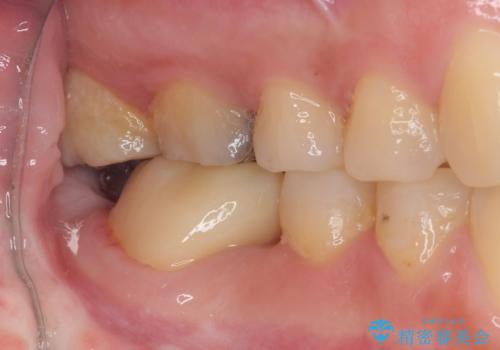

- 1本欠損したままの奥歯の治療を終えたいとのことで来院された患者様です。

奥歯が1本欠損した状態で矯正治療を行っていたそうですが、どのように治療を終了させるか未決のまま矯正装置を除去してしまい、暫く放置されている状態でした。

理想的には残っている歯のスペースを詰め、最後方にインプラントを埋入することが理想的ではありますが、矯正治療期間や費用の面から、前後に歯を大きくする補綴治療を行うことで対応することとなりました。

矯正装置を長いこと付けていたことで、歯が大きく捻転してしまい、舌に当たる感覚を気にしていらっしゃいましたが、補綴治療により捻転とともに解消することができました。

上顎の最後臼歯と咬み合わせるために前後径が大きくなっており、歯肉周りに汚れが溜まりやすくなるため、日々の清掃と定期的なクリーニングが必要となります。